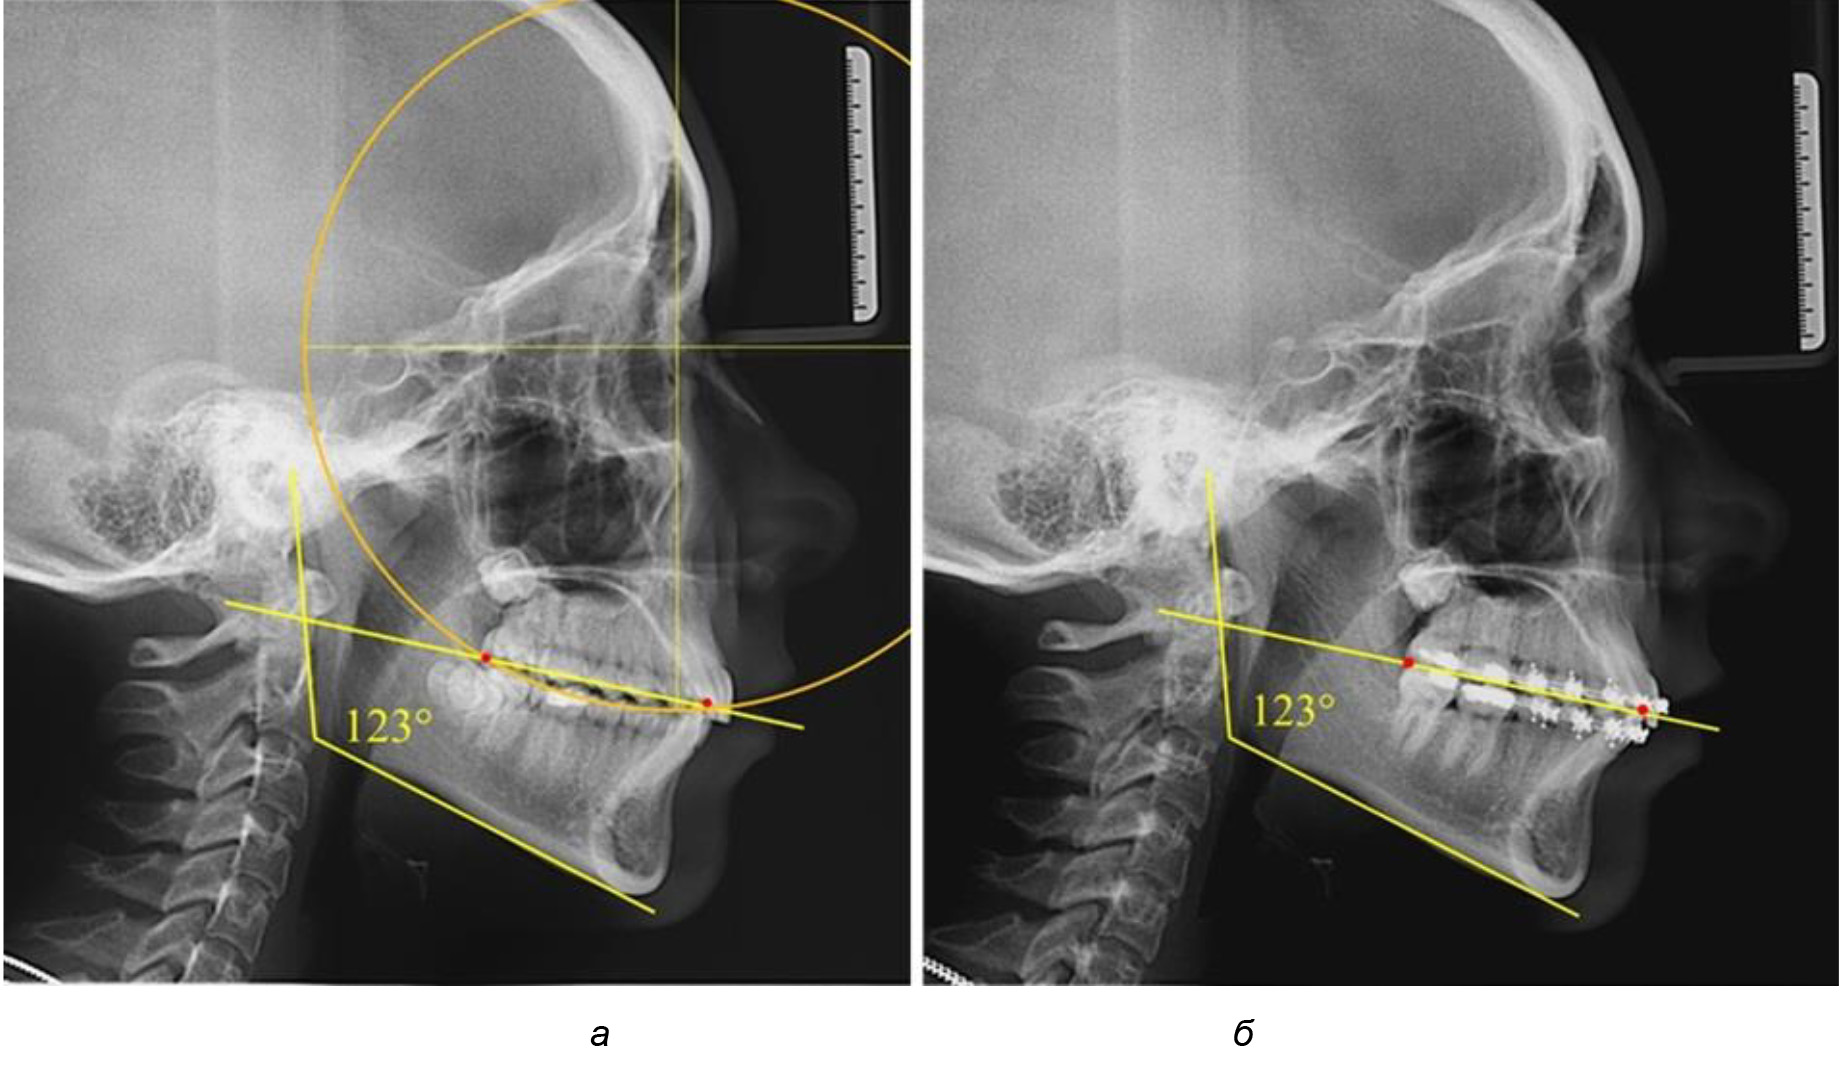

На рентгенограммах людей 2-й подгруппы (30 человек с нейтральным типом роста) величина угла нижней челюсти в среднем составила (120,34 ± 2,19) ° и характеризовала нейтральный тип нижней челюсти.

Глубина кривой Spee в среднем по 2-й подгруппе составил (3,54 ± 0,58) мм, что было незначительно меньше, чем при анализе аналогичного показателя 1-й подгруппы.

Достоверных различий с показателями, полученными при анализе ТРГ и ОПТГ, нами не отмечено (р ˃ 0,05). Деление величины радиуса круга к длине окклюзионной линии составило 1,612 ± 0,02, что, так же как и в 1-й подгруппе, было близким по значению к числу Фибоначчи (1, 618).

Рис. 3. Особенности кривой Spee на ТРГ (а) и ОПТГ (б) при нейтральном типе роста нижней челюсти